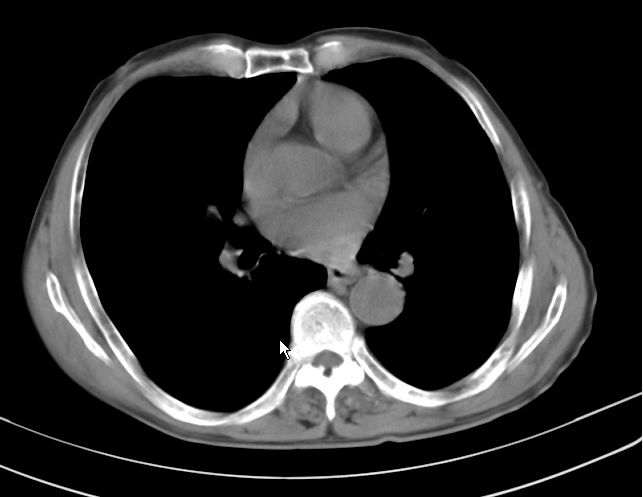

请大家看看是什么性质的。炎性病变首先考虑哪一种炎症。

楼主说是炎症,凭啥?典型的周围型肺癌(腺癌可能性大),肝内可能已有转移,强化看看吧。